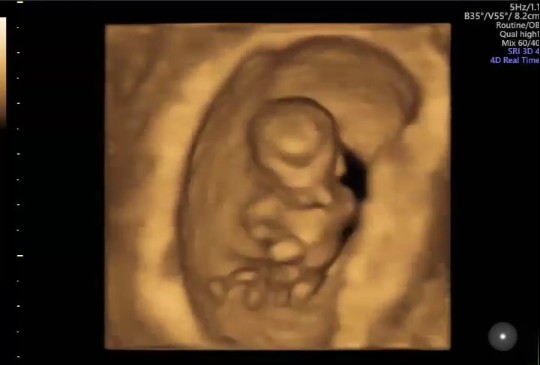

bayi 9minggu udh keliatan apa ya kirakira

Bun kalo hamil usia 9minggu bayi udh keliatan kaya gimana ya